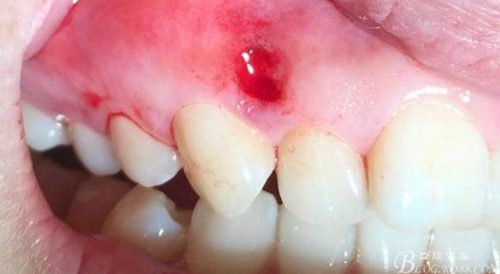

1.0-1.3*17mm工作尖 100mj 25-30Hz去除色素后即刻

術(shù)后24小時